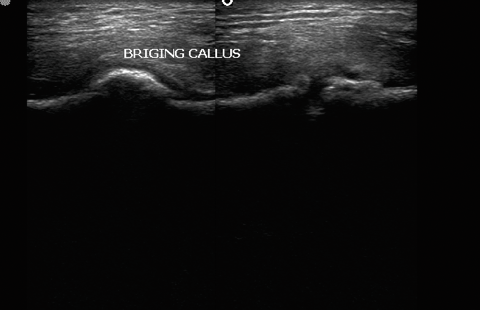

Callus formation.

Callus formation helps to identify the region sometimes not seen on skiagrams

Cortical breach with intervening gap fills up with hypoechoic granulation tissue, evolving into bony matrix. This process is sonographically accessible to evaluation with greater accuracy and sensitivity in predicting optimal vs sub-optimal healing . Early intervention at 4-6 weeks post fracture can help reduce morbidity dramatically

OSSEOUS STAGE : Echogenic callus with acoustic shadowing and obscured medullary cavity / IM nail …5-6 wks